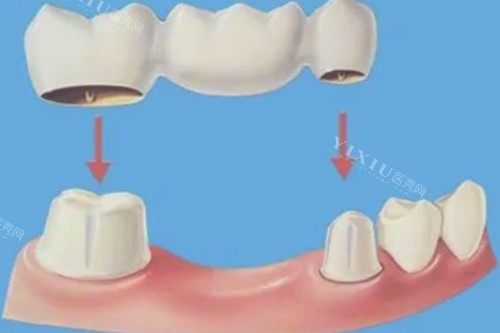

烟台芝罘医院口腔科镶牙价格表

牙齿镶牙:772 - 1540 元起

镶牙修复:1517 - 2487 元起

靠前镶牙方式:3109 - 8353 元起

镶牙冠:1729 - 4484 元起

固体桥镶牙:936 - 4357 元起